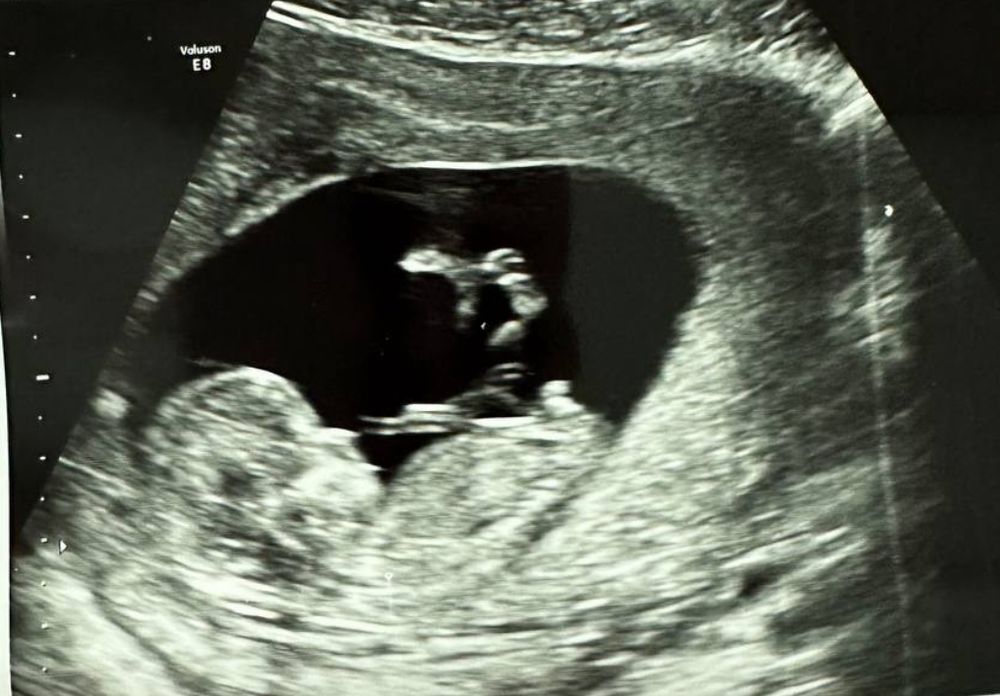

Была на первом скрининге в 13.4 недель, предположительно сказали, что будет девочка, но что-то меня терзают большие сомнения) А кого вы видите на фото?) или по личному опыту можете предложить, какой пол у малыша) И были ли у вас случаи с ошибкой пола на узи? Спасибо заранее

У меня точно такое же УЗИ. Не знаю, где они там девочку увидели, это мальчик. Как врач конечно точно не скажу, но очень похоже

Я за мальчишку))) вон какой стручок вверх торчит👍🏼 у девочки не так выглядит все